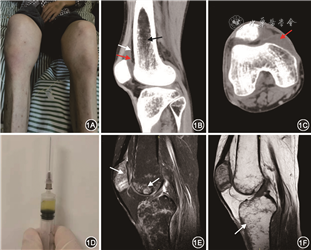

患者男,33岁。有同性冶游史。因“发热、对称性多关节肿痛1周”于2018年10月26日入院。患者入院前1周出现发热,热峰39.2 ℃,伴双肘关节和双膝关节疼痛,不能行走,无晨僵。当地医院予左氧氟沙星等不规则抗感染治疗,体温逐渐恢复,但关节肿痛未改善,并新增双侧踝关节肿痛,活动受限。病程中患者无咳嗽,无腹痛、腹泻,食纳及睡眠欠佳,大小便正常。患者半年前确诊人类免疫缺陷病毒(HIV)抗体阳性,基线CD4+T淋巴细胞计数4个/μl,HIV RNA 4.95×105拷贝/ml,启动拉米夫定(3TC,300 mg/次,1次/d)、富马酸替诺福韦二吡呋酯(TDF, 300 mg/次,1次/d)以及依非韦伦(EFV, 600 mg/次,1次/d)抗反转录病毒治疗(ART)。否认外伤、针灸及关节注射史。入院体检:体温36.2 ℃,心率99次/min。浅表淋巴结未及肿大。双肺呼吸音粗,未闻及干湿啰音。腹平软,全腹无压痛、反跳痛,肝脾肋下未及。双侧肘关节、双侧膝关节、双侧踝关节明显肿胀,局部皮肤潮红,触痛阳性(图1A),受累关节稍活动即疼痛难忍,活动明显受限,不能站立和行走。入院完善相关检查:血常规示白细胞6.8×109/L,中性粒细胞86.3%,血红蛋白93 g/L。血乳酸脱氢酶166 IU/L,尿酸166 μmol/L。血降钙素原7.25 μg/L,C反应蛋白430.3 mg/L,红细胞沉降率129 mm/1h,类风湿因子3.1 IU/ml,抗链球菌溶血素“O”试验81.8 IU/ml。抗核抗体、抗心磷脂抗体、抗双链DNA抗体、抗中性粒细胞胞质抗体均阴性。血培养阴性,结核感染T细胞γ干扰素释放试验无反应性,血结核抗体阴性。CD4+T淋巴细胞计数9个/μl,HIV RNA 5.34×104拷贝/ml。胸部CT示左肺下叶2 mm小结节,纵隔、两侧肺门、锁骨区淋巴结肿大;膝关节CT示关节积液,周围骨质欠均匀(图1B、1C)。膝关节腔穿刺抽出少量淡黄色关节腔积液(图1D),双侧关节腔积液抗酸染色均为阳性(2+),关节腔积液(罗氏固体培养基2+;接种至阳性报告时间为5周)以及血分枝杆菌培养均为阳性(BACTEC MGIT906液体分枝杆菌培养系统;2次阳性;接种至阳性报告时间分别为5周和4.5周),菌种鉴定为鸟分枝杆菌(包括未培养和培养后的样本;检测方法为PCR-反向点杂交法)。

住院第18天,根据关节液培养和菌种鉴定结果诊断为鸟分枝杆菌关节炎,予阿奇霉素(0.5 g/次,1次/d)、利福布汀(0.15 g/次,1次/d)、乙胺丁醇(1 g/次,1次/d)和莫西沙星(0.4 g/次,1次/d)联合抗分枝杆菌治疗,以及地塞米松(5 mg/次,1次/d)抗炎治疗。患者关节肿痛逐渐改善,糖皮质激素逐渐减量。抗分枝杆菌治疗16d,患者双肘关节、双膝关节、双踝关节肿胀消失,关节压痛仍阳性,关节活动度均稍增加,但仍不能站立。患者出院并继续口服上述药物抗分枝杆菌治疗。抗分枝杆菌治疗4个月,患者可搀扶站立,但无法行走,复查膝关节磁共振成像(MRI)示关节腔积液较前改善(图1E、1F)。再次行关节腔积液检测:抗酸染色阴性,分枝杆菌培养阴性。抗分枝杆菌治疗9个月,患者一次可缓慢行走1 km,无关节疼痛,但关节活动度仍低于正常。